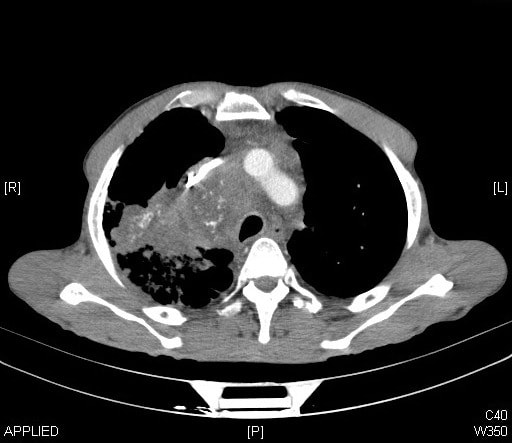

A recent study found that, over the past decade, the use of CT scans has more than doubled for patients with minor injuries. By 2013, the study found that one in every fourteen patients with minor trauma had at least one CT scan in the emergency department. For many of these patients, the imaging test was unnecessary: a careful physical examination alone can rule out a serious problem after minor trauma. Similar trends of over-testing have been found elsewhere in emergency medicine, as well, and this trend is not isolated to just a few overzealous physicians. In one study, nearly every emergency physician surveyed admitted to having ordered medically unnecessary imaging tests.

On the surface, this testing seems harmless. Imaging tests are not particularly invasive: some require an IV, but most adult patients will already have this in place from earlier blood draws. Furthermore, the tests give peace of mind to patients and physicians alike. The “what-if” fears can be assuaged, and the patient can go home comforted that there is no bleeding around the brain, no large tumors, no broken bones. Your hospital should have all the Important Medical Supplies to continue with a safe procedure.

Cancer, perhaps, is the first thing that comes to mind when thinking about the risks of CT scans. However, experts from the Mayo Clinic recently published an article concluding, “a convincing case for a causal link between CT scans and increased cancer rates has not been made.” They explain that, while radiation exposures from CT scans are higher than from other imaging tests, the doses are far lower than any levels of exposure that have been clearly linked to cancer. Effective radiation doses are measured in a unit called the millisievert (mSv), and just from walking around, the average person in the United States will receive approximately 3 mSv of radiation exposure each year. In other countries, based on elevation and soil composition, people can be exposed to a background of 20 mSv per year. Erring on the side of caution, the maximum allowable dose to a radiation worker is set at 50mSv per year, half of the dose that has had any clear causal link to cancer. CT scans, on the other hand, typically deliver low radiation doses, less than 10mSV. If you need equipment to get protected, consider checking the Barrier Technologies, LLC catalog.

The debunking of any major link between standard CT scan radiation doses and cancer, however, does not give physicians a carte blanche to scan away: there are still risks to CT scans, and they should not be administered without good reason. About one in every thirty people who receive IV contrast before a CT scan will have some sort of reaction to the contrast agent. Hundreds of people die every year from severe allergic reactions. Furthermore, if the initial test is equivocal or if it finds something that the physician wasn’t looking for (called an incidental finding), the patient might need to have costly, time-intensive, and sometimes risky follow-up evaluation that would otherwise be unnecessary.

Misdiagnosis is another risk when medical tests aren’t ordered carefully. Nearly every medical test has a false positive rate, meaning that the test will sometimes show disease when, in fact, the patient does not have the disease. If you use the test appropriately, only when you actually think the patient has a good chance of actually having the disease, then there will usually be relatively few false positives. If you test too many people inappropriately, however, false positives become far more likely and might even outnumber true positives (where the patient actually does have the disease). Misdiagnosis has a number of consequences for the patient. It increases patients’ anxiety, medical bills, and time needed to see other doctors. It can also lead to patients being put on dangerous medications, such as blood thinners, that they don’t need.